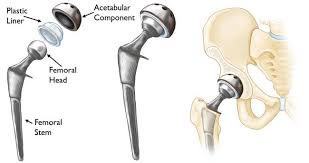

وبشكل عام فإن المفاصل الصناعية للفخذ تتكون من ثلاثة أجزاء: السبيكة المعدنية والسطح الناعم والمادة التي تربط المفصل وسبائكه بعظام الإنسان.

السبائك المعدنية يتم تصنيعها من أنواع خاصة تتحمل الضغوط وتكرار الحركة والاحتكاك، ويتم تصنيع هذه السبائك من مواد يتقبلها الجسم ويعتبرها جزءا منه.

الأسطح الناعمة فيمكن أن يكون من نفس السبيكة المعدنية التي تم تصنيع المفصل منها أو يكون جزءا من المفصل متكون من مواد بلاستيكية، تسمى البولى إيثيلين لمنع الاحتكاك أو بمعنى أدق تقليله.

المفصل السيراميكي وهو من الأنواع المميزة التي يتم الاعتماد عليها بدلا من مادة البولى إيثيلين لتقليل الاحتكاك مثل السيراميك

أما بالنسبة لطريقة تثبيت المفصل في العظام، فهناك أنواع عديدة منها أسمنت العظام، وهو مادة تربط المفصل بتجاويف العظام، ومنها مادة الهيدروكسى أباتيت وهى مادة يتفاعل معها العظام وتلتئم معها مثل التئام الكسور، ومنها أسطح أخرى للمفاصل تسمح بنمو خلايا العظام بداخلها والتصاق العظام بالمفصل.

توجد أشكالا كثيرة ومتنوعة للمفاصل بحيث تناسب حالة المريض فمنها أنواع مستقيمة وأنواع أخرى منحنية وأنواع قصيرة للدخول في تجويف عظمة الفخذ، ومن ناحية أخرى هناك أيضا أشكال وأنواع كثيرة لمفصل الحوض، حيث تناسب شكل مفصل المريض وتناسب حالته.

انواع مفصل الفخذ السيراميكي بالصور

عملية اختيار نوع المفصل من أهم الخطوات التي يجب إتباعها والتي يتوقف عليها نجاح العملية أو فشلها، حيث يقوم الطبيب بتحضير أنواع مختلفة من المفاصل حتى تناسب حالة المريض لتحقق الوظيفة المطلوبة بدرجة نجاح عالية، كما أن هناك تفاصيل أخرى كثيرة يجب مراعاتها في التخطيط للجراحة وتنفيذها لضمان نجاح العملية، وأغلب المفاصل الصناعية يتم السماح للمريض فيها بالمشي من اليوم الأول بعد الجراحة بشرط توفر العوامل المناسبة لاستقرار المفصل والتئام الأنسجة العضلية المحيط.

وتوجد عدد من العوامل الهامة التي على أساسها يتم اختيار المفصل المناسب، ويتم تقسيم أنواع المفاصل حسب تقسيمات كثيرة:

حسب طريقة التثبيت في العظام: ويتم تقسيمها إلى مفصل إسمنتي ومفصل غير إسمنتي

حسب نوع السطح الناعم إلى مفاصل معدنية على سطح بولي إيثيلين، أو سطح معدني على سطح معدني،سطح سيراميكي على بولي ايثيلين، أو سيراميكي على سيراميكي.

حسب تصميم المفصل ويتم تصنيفه إلى مفصل قصير ومفصل طويل ومفصل قصير جدا

حسب غطاء السبيكة المستعملة في جزء الخاص بعظمة الفخذ إلى ومنه أنواع تايتانيوم وهايدروكسي اباتيت او ذوي الثقوب المتعددة

حسب مقاس رأس عظمة الفخذ : 28، 32، 38، أو ثنائي القطب أو رأس أكبر.

حسب تصميم قاعدة حق مفصل الفخذ و طريقة تثبيتها بمسامير او بدون مسامير.

حسب تصميم المفصل من النوع ثابت الشكل أو القابل للتغيير حسب العظام الناقصة modula r.